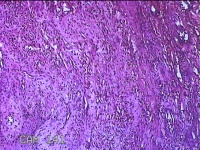

右侧食指远端结节

性别

男

年龄

47岁

临床诊断

皮下结节

一般病史

发现右侧食指3天。

标本名称

大体所见

灰白暗红色带皮肤样结节1.2x0.7x0.3cm一个,表面糜烂,切面灰白粉红色,质中。